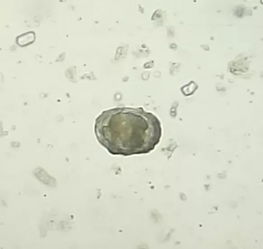

2、球虫

球虫主要是寄生在小肠粘膜和细胞上面,尤其是对于狗狗来说,更要小心注意球虫的产生,否则可能会引起一些较为严重的后果。